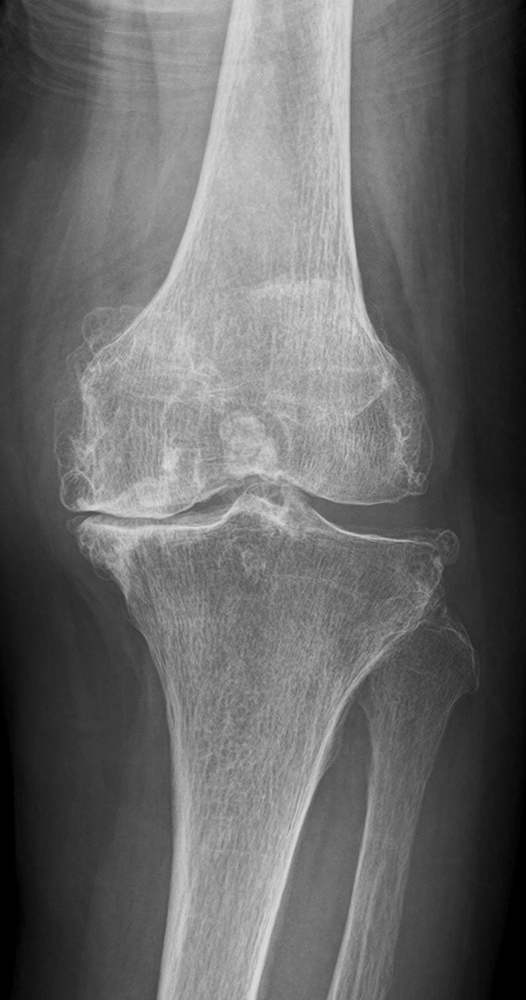

変形性膝関節症は一次性と原因疾患に続発する二次性に分類されます。

わが国では年齢による退行性変化を主因とする一次性が多く、軟骨のすり減り、骨棘(骨のとげ)を伴い、多くは内反変形(O脚)を呈します。女性に多く、特に肥満との関連が強いといわれています。膝関節には歩行するだけで体重の3倍の力がかかるといわれており、病状の予防や進行を抑えるためには体重のコントロールが最も重要です。

傷んだ関節表面を人工関節の形に合わせて削り、金属、セラミック、ポリエチレンでできた人工関節を骨の上に固定します。人工関節の耐久性は10年間弛みなく日常生活が送れる可能性が95%以上といわれ、長期的にも安定した方法です。

手術前